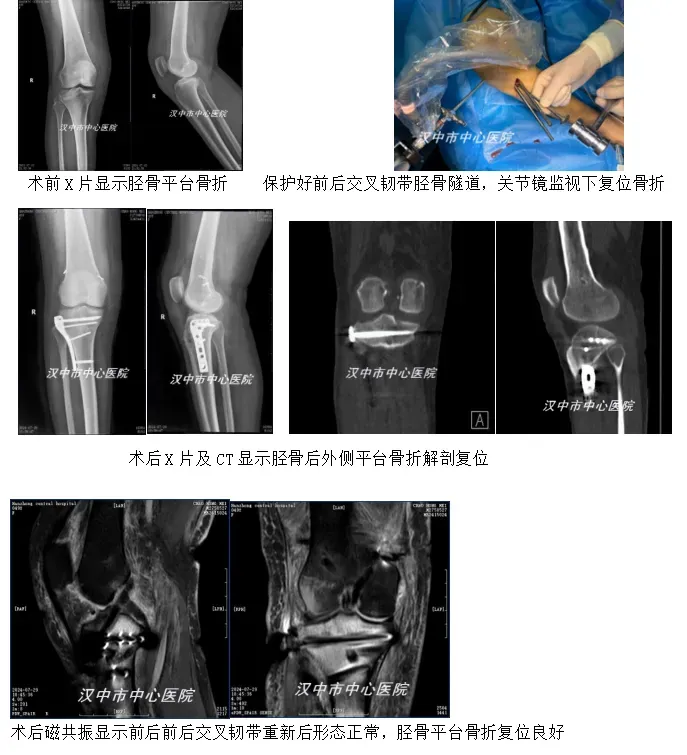

骨关节创伤科运动医学团队接诊后,详细询问患者病史及体格检查后,结合影像学检查,查阅相关文献资料,通过反复研究,决定为其一期关节镜下取自体肌腱重建前后交叉韧带,以及修复内侧副韧带,同时关节镜下监视下复位固定胫骨后外侧平台骨折。该手术难度大,本身膝关节多发韧带一期手术治疗属高难度手术,同时还要复位固定骨折,这需要在较短的时间内完成,否则手术时间过长会导致膝关节灌注液外渗产生小腿骨筋膜室综合征,此外还存在胫骨平台骨折手术过程中,钢板螺钉骨道容易同前后交叉韧带骨道冲突,可能会损伤重建的前后交叉韧带等一系列问题。

经过术前充分准备,在阮文辉主任的指导下,谢鹏主任医师运动医学团队仅用2小时左右就顺利完成了手术,术中先行前后交叉韧带骨道制作,用钻头插入骨道占位保护骨道不被螺钉破坏,骨折复位良好钢板螺钉放置结束后,再去掉骨道钻头,拉入肌腱固定。术后患者按照科室护理康复团队制定的早、中、晚三期康复方案持续康复锻炼。术后1月到门诊复查证实患者骨折愈合良好,膝关节功能恢复良好,得到了患者及家属的衷心感谢。